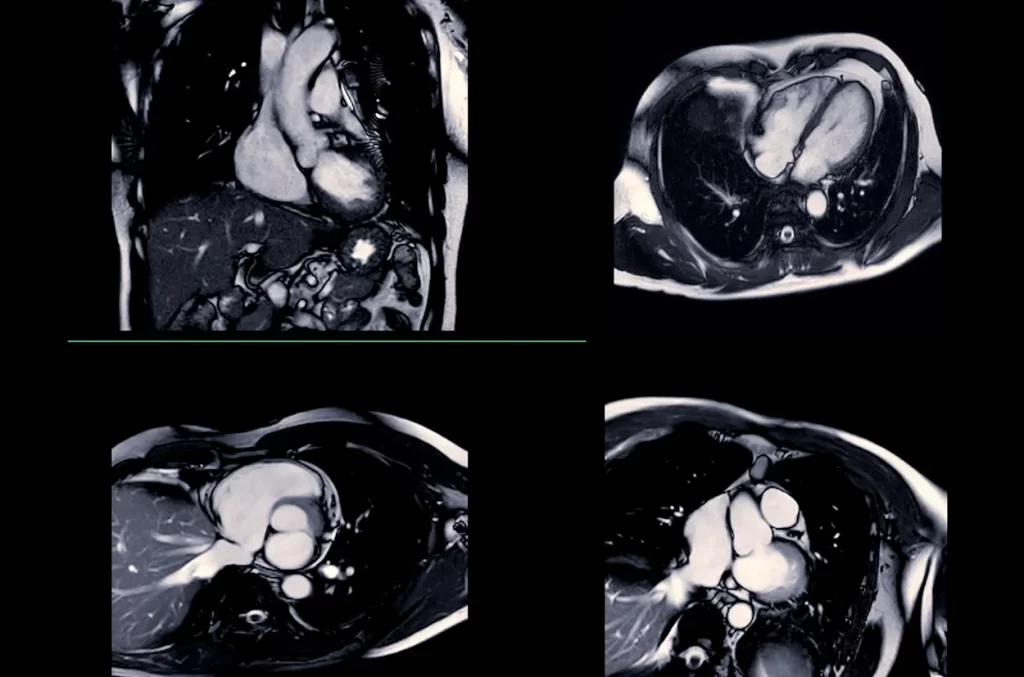

Cardiac MRI

A highly detailed imaging test that uses magnetic resonance technology to create precise pictures of your heart’s structure and function.

How it happens: You’ll lie comfortably inside an MRI scanner while the machine creates detailed images of your heart. The procedure is painless and typically takes 30-90 minutes. Unlike standard X-rays or CT scans, no radiation is used.

When it’s necessary: A cardiac MRI may be recommended to evaluate heart muscle damage, inflammatory conditions, congenital defects, heart tumors, or to assess the severity of heart disease.